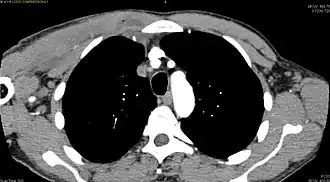

CT with IV contrast showing enlargement and heterogeneous hypodensity in the right pectoralis major muscle. A focal abscess collection with gas within it is present medially. There are enlarged axillary lymph nodes and some extension into the right hemithorax. Note the soft tissue and phlegmon surrounding the right internal mammary artery and vein. The patient was HIV+ and the pyomyositis is believed to be due to direct inoculation of the muscle related to parenteral drug abuse. The patient admitted to being a "pocket shooter" -

CT exam showing a multiloculated fluid collection in the left gluteus minimus muscle found to be a staph aureus pyomyositis in a 12-year-old healthy boy.